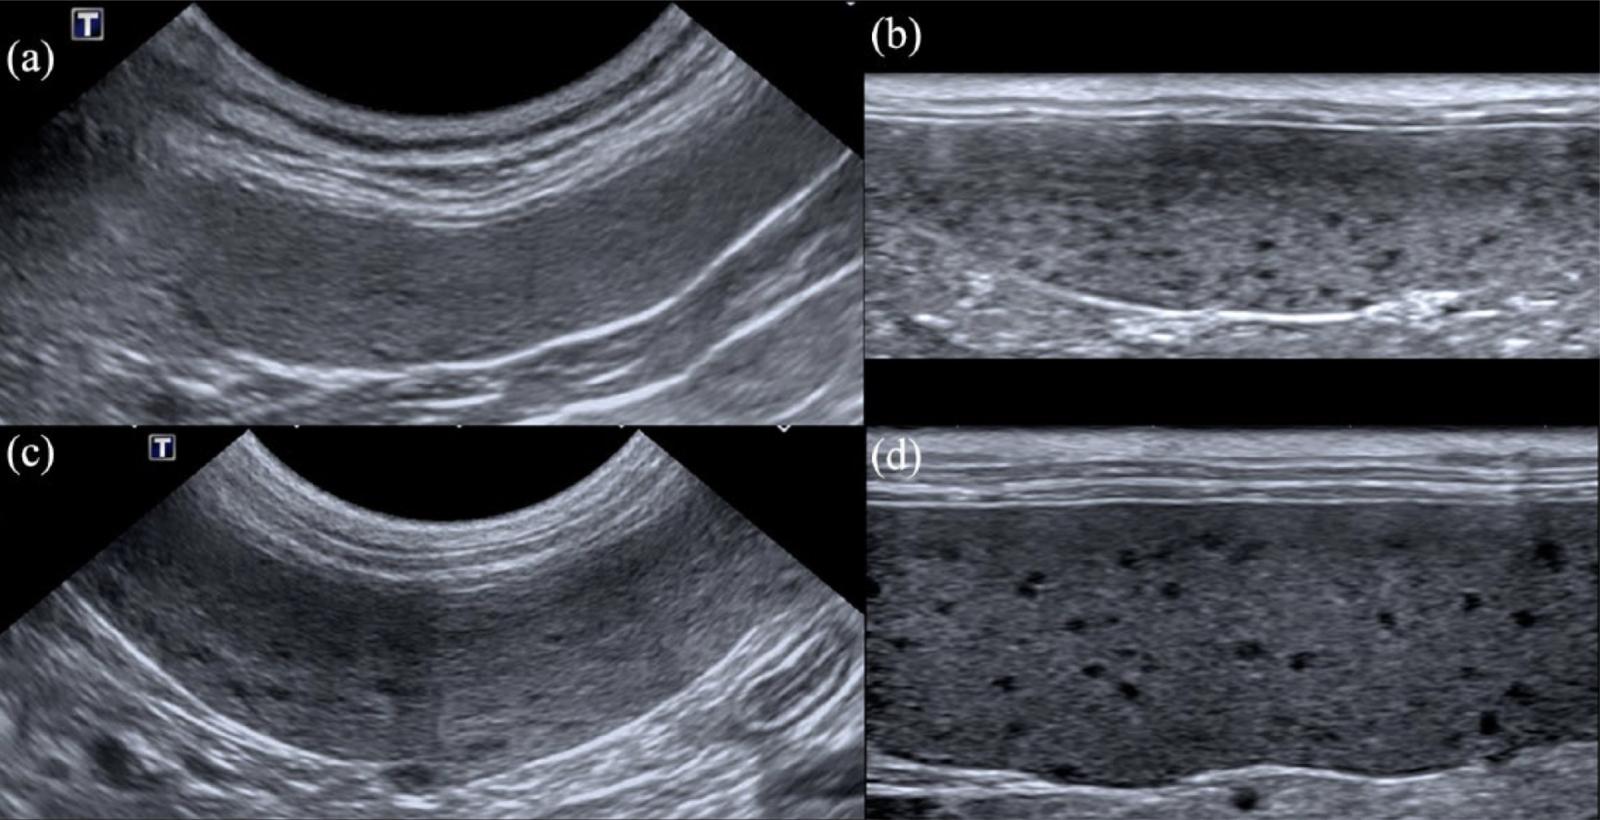

Dnes bych chtěl sdílet výsledky ze studie [1], která se zaměřila na diagnostickou hodnotu ultrazvukového vyšetření sleziny u dospělých koček. 🐈 Konkrétně se zabývala tzv. „honeycomb“ vzhledem, který můžeme přeložit jako vzhled včelí plástve (voštinový). Někdy taky označován pojmy „Swiss-cheese-like“, „moth-eaten“ nebo „mottled“. V parenchymu takovéto sleziny jsou diseminované multipní malé hypoechogenní noduly.

Autoři doporučují provádět vyšetření sleziny u koček i vysokofrekvenční lineární sondou, která má vyšší šanci pro zjištění tohoto vzhledu a následně doplnit o aspirační biopsii pro potvrzení diagnózy. Uvedená zjištění však neplatí pro psy. O tom zas někdy příště.